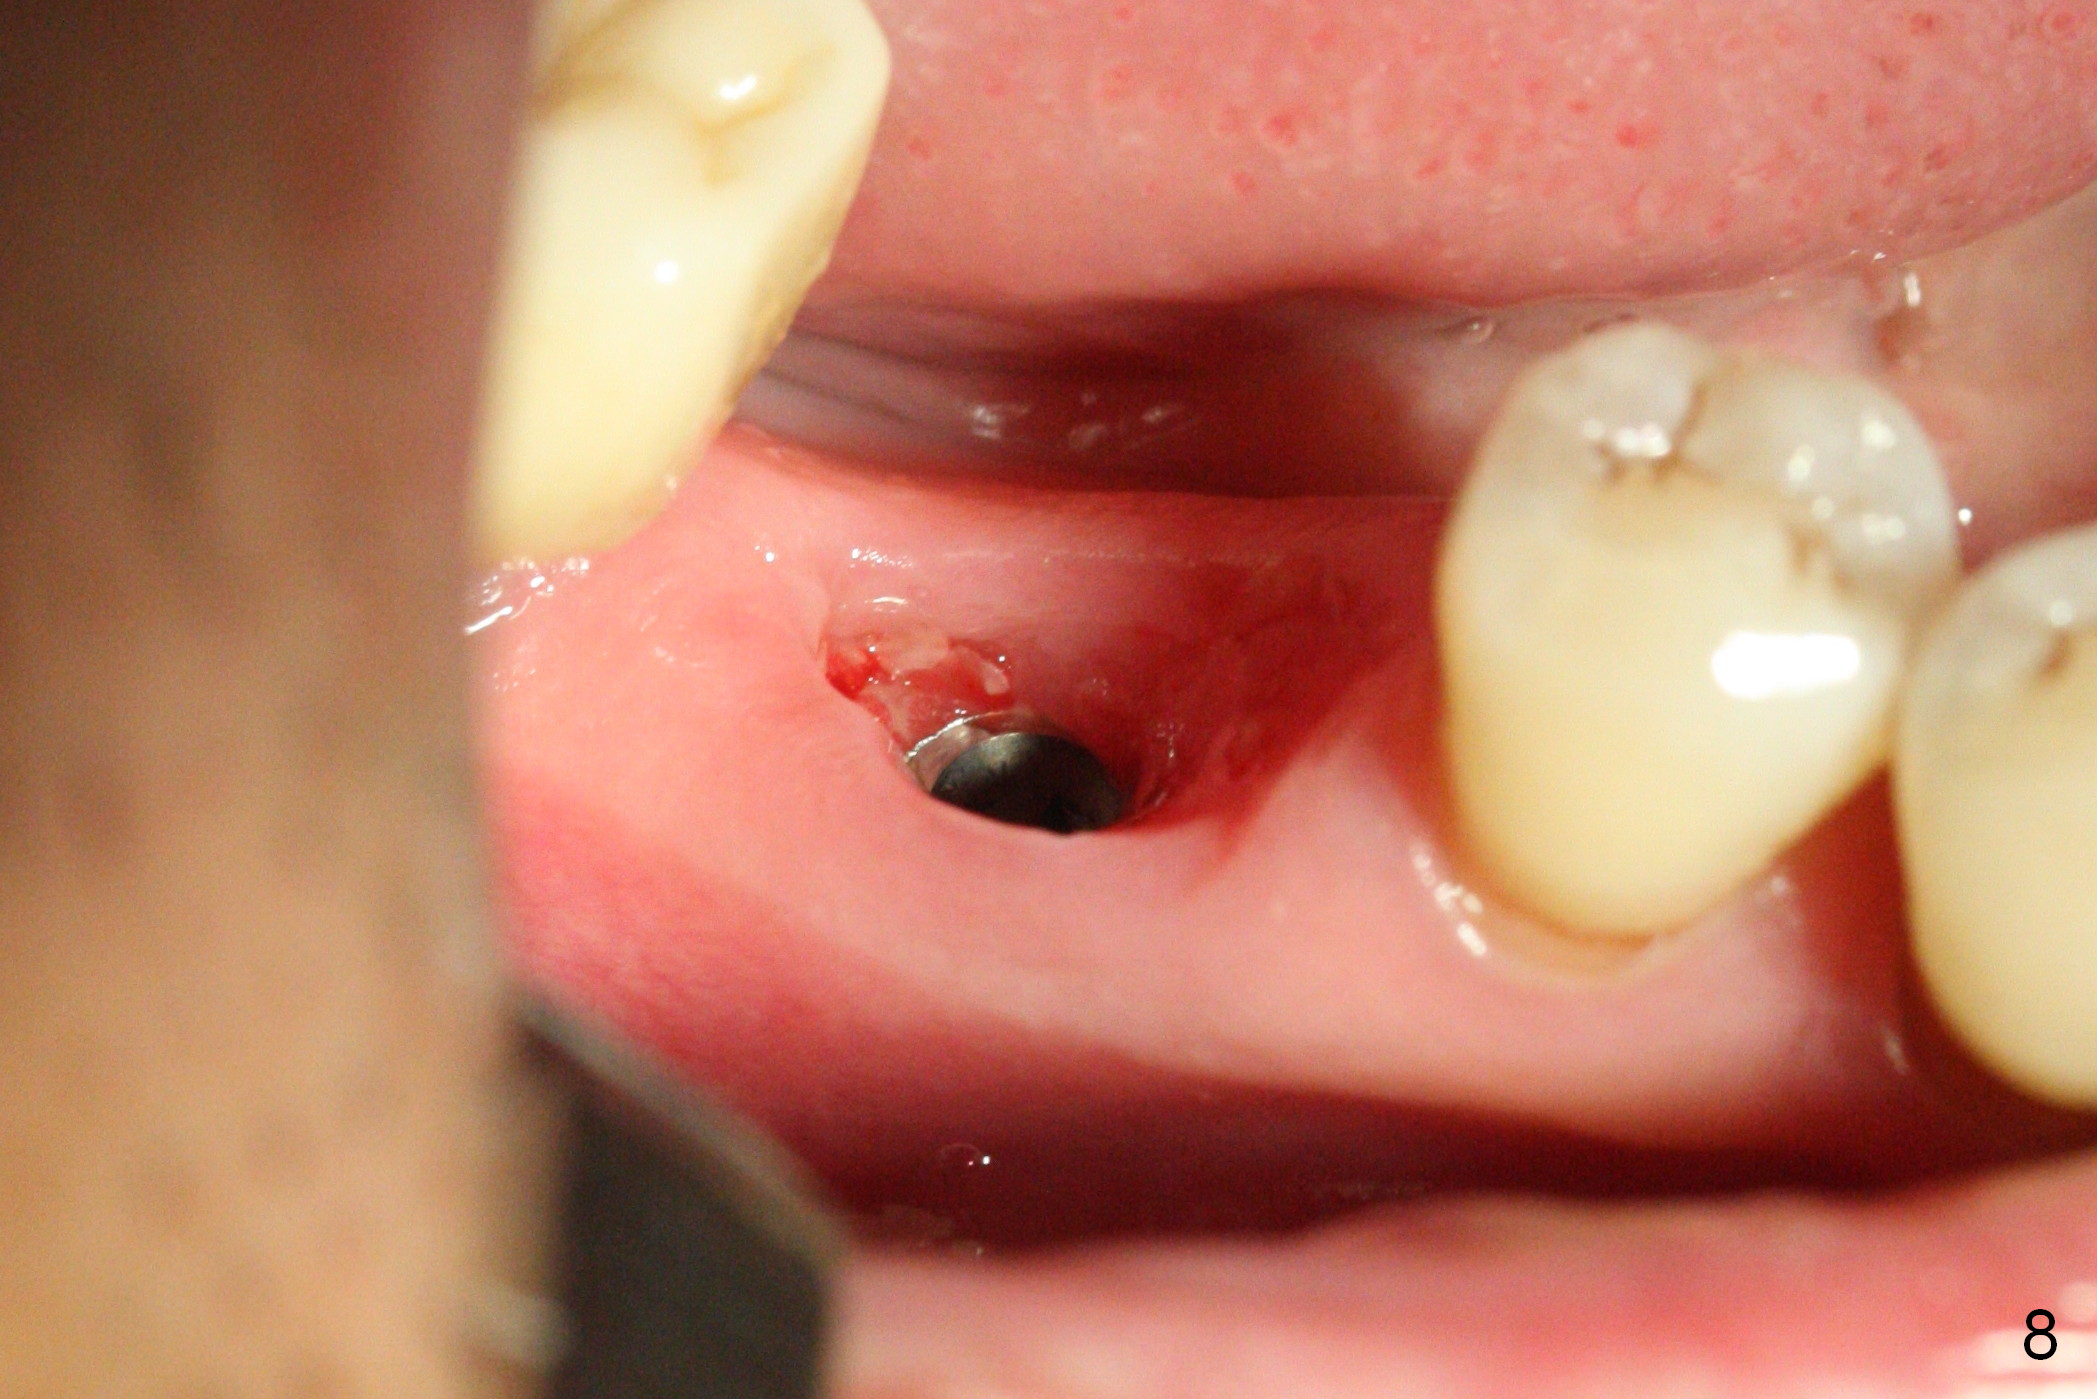

Extraction shows the large distal socket (Fig.1 D) and the thin and low septum (*) of the tooth #30. After Magic Split test confirms hard bone, osteotomy is initiated with 1.6 mm pilot drill with 11 mm stopper (Fig.2); there is 2.7 mm distance to the Inferior Alveolar Canal. Following Marking Bur, a 4.8 mm Magic Drill is used to finish the osteotomy with difficulty because of hard bone and ineffective local anesthesia due to infection. A 5x9 mm "dummy" implant is placed to determine the placement level relative to the distal crest (Fig.3 *). After removal of the dummy implant, an authentic one with the same dimension is placed with packing abundant allograft (.5-1.5 mm) and Osteogen (Fig.4 *); it appears that 4 to 5 threads (fins) of the implant (arrowheads) are engaged to the native bone for primary stability (>40 Ncm). Later more bone graft is placed distally (Fig.5 arrow). With the short implant placed not so deep, there is 6-7 mm clearance from the underlying canal (Fig.6). The patient is doing well 7 days postop (Fig.7). He feels that the provisional is too bulky buccally for the first 2 days postop. The buccal margin will be trimmed in another 2 weeks (dashed line). The patient in fact masticates on the right side postop. By the time he returns for provisional revision 1 months 10 days postop, he has mild pain. There is food entrapment. The provisional and the abutment are slightly loose, whereas the implant is stable with healing socket (Fig.8). A healing abutment is placed. The implant appears unstable nearly 5.5 months postop. The gap between the bone and implant seems to be large (Fig.9). The implant should have been larger and longer for fast healing. A healing screw is used instead. The site heals 10 months postop with an increase in bone density around the implant (Fig.10.) Prior to cementation of the final crown, the abutment is minimally exposed (Fig.11 (6.5x5.7(3) mm)). In fact the abutment screw becomes loose 2 months post cementation (1 year postop); it appears that crown/implant ratio is unfavorable (Fig.12). The implant is slightly placed mesially (cantilever). The patient cannot chew on the left. The tooth #19 is periodontally affected and the tooth #18 is missing. When bone loss is severe, the implant should be as large as possible and preferably tissue-level. The abutment screw is re-loosening 1.5 years post cementation (4 months post #19 socket preservation, Fig.13). The crown/implant ratio at #31 is more favorable than that at #30 (compare black lines). The crown at #31 has large contact area with the tissue-level implant (external), whereas the contact between the abutment and the bone-level implant is much less (internal). To prevent the abutment screw re-loosening (turning) in function, a screw driver (Fig.14 D) will be buried inside the crown/abutment after the screw is retightened. Make sure that the driver is in the middle of the access hole. Section the driver in situ obliquely (Fig.15); flat sectioning allows the driver to turn with the abutment screw in function. After insertion of plumber tape around the sectioned screw driver, use composite to fix the driver in place and seal the access hole (Fig.16). Occlusal check suggests weak link between the abutment and bone-level implant at #30.